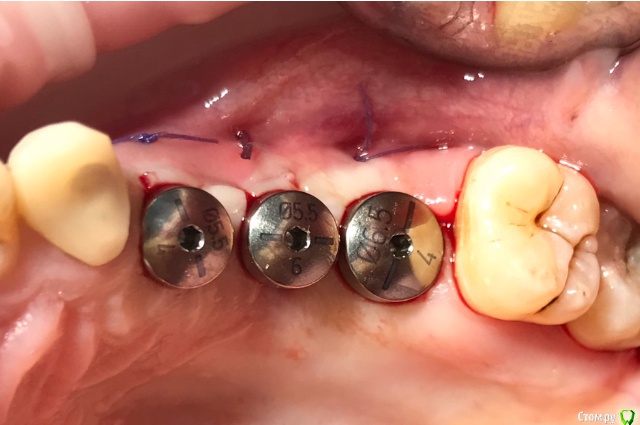

колесников Опубликовано 20 августа, 2019 Автор Поделиться Опубликовано 20 августа, 2019 Очередной случай тоннельной пластики альвеолярного гребня. Был небольшой бонус в виде лунки 26го зуба с дефектом вестибулярной стенки и оас. Лунка консервирована и закрыта «быстрым Ноймайером»,24,25 тоннельный графтинг. Графт тот же,шурос кортикальный без добавок.Контроль и имплантация через 4 мес,через неделю фиксация временной реставрации. Через 2-3 проверим на состоятельность. 4 Ссылка на комментарий